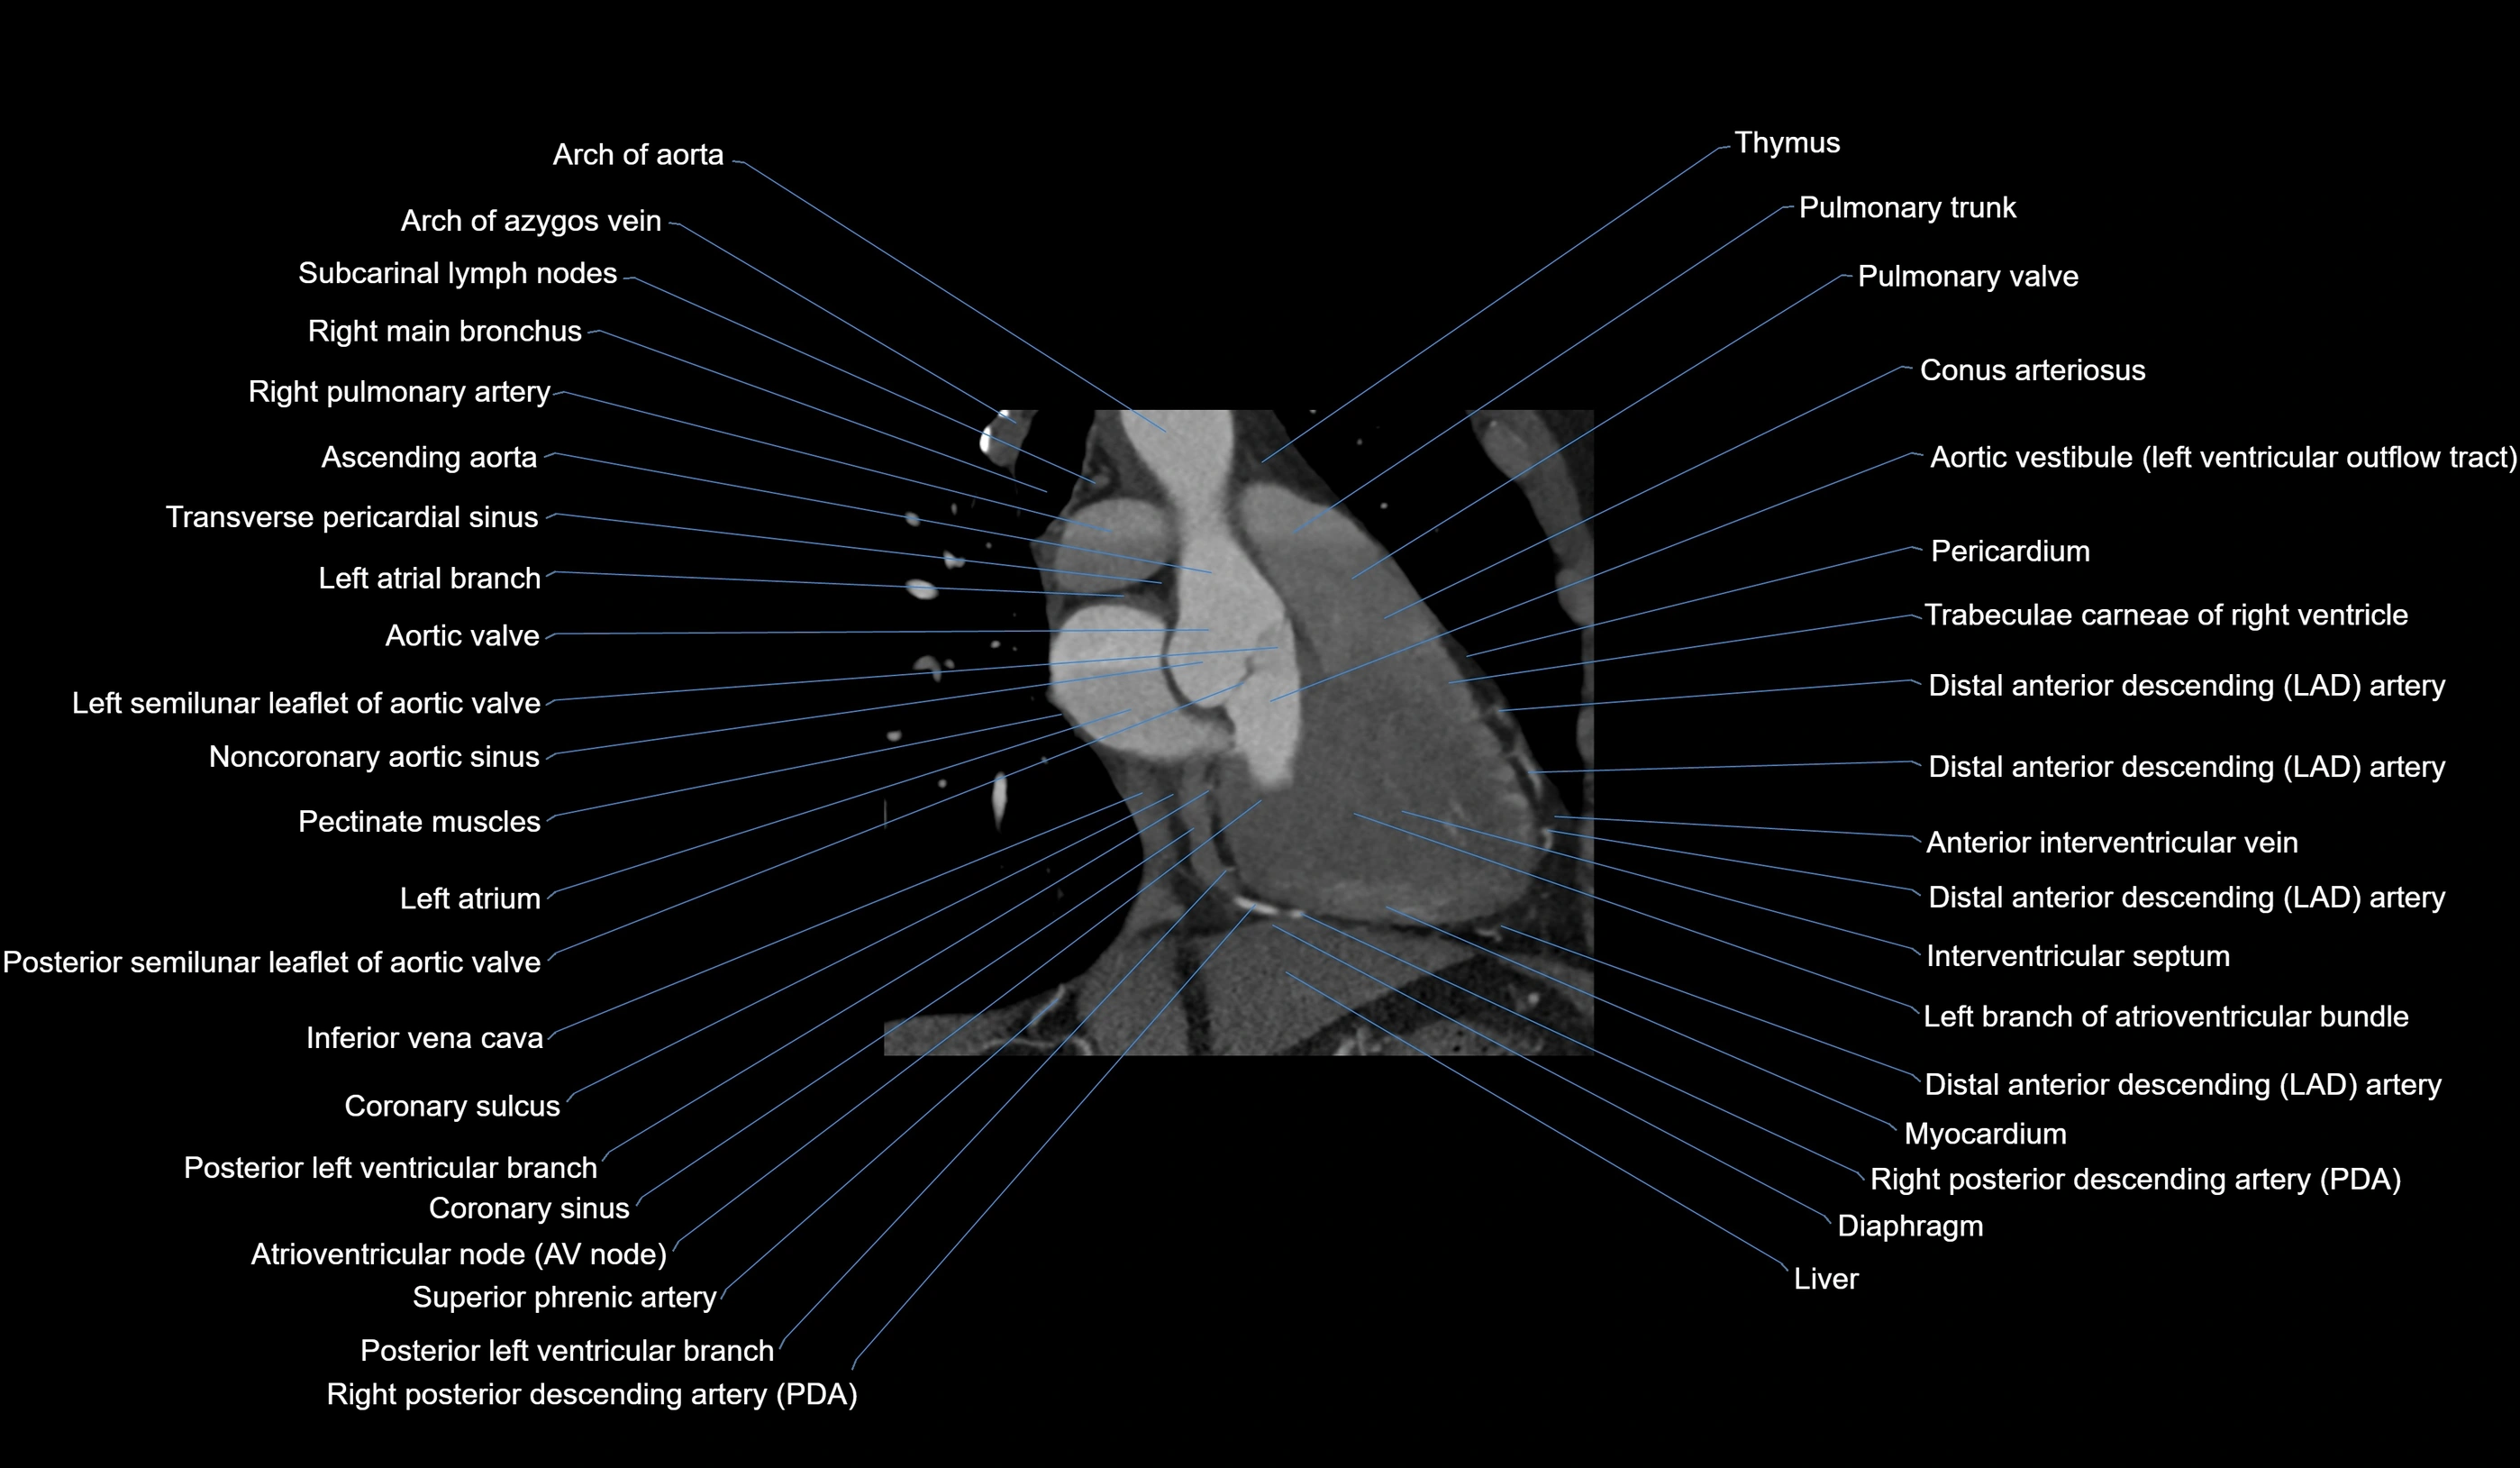

CT images